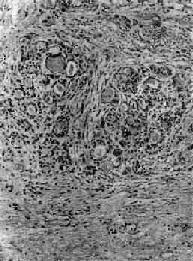

2.纤维性甲状腺炎(fibrous thyroiditis)又称Riedel甲状腺肿,甚少见,主要发生在中年妇女,病因不明。病变多从一侧开始,甲状腺甚硬,表面略呈结节状,与周围明显粘连,切面灰白。镜下,甲状腺滤泡明显萎缩,纤维组织明显增生和玻璃样变,有少量淋巴细胞浸润(图15-8)。临床常有甲状腺功能低下。

图15-8 纤维性甲状腺炎

甲状腺滤泡萎缩,纤维组织明显增生,有少量淋巴细胞浸润